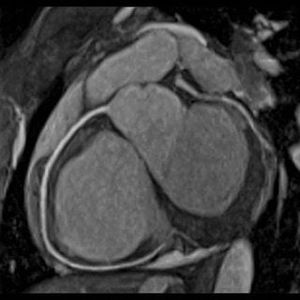

Balanced steady-state free precession (b-SSFP) techniques (TrueFISP/FIESTA/bFFE) sequences are widely used for non-contrast enhanced (NCE) MRA of the chest, abdomen, and pelvis. TrueFISP/FIESTA are rapid gradient-echo sequences in which the free induction decay (FID) and spin/stimulated echo components are made to coincide in the middle of the TR interval. This structure allows a coherent transverse steady state to become established, whose maximum signal intensity depends on the ratio T2/T1 of the tissue being imaged. Small vessels such as the coronary, renal, or mesenteric arteries may be obscured by high signal from the nearby fat (high T2/T1 ratio such as blood and CSF) in which they are embedded. Commonly an adjuvant fat suppression method is used when performing b-SSFP MRA of these vessels. Figure shows a gated bSSFP coronary artery image with fat suppression.